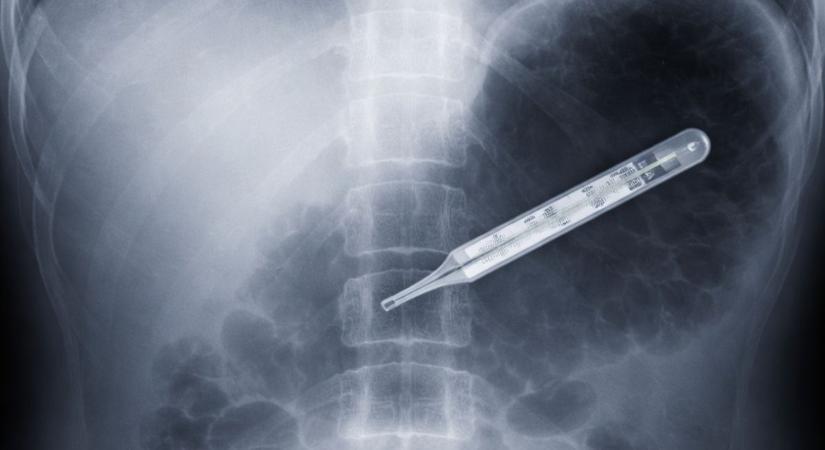

Gyomorfájdalmakra panaszkodott: 20 évig élt higanyos hőmérővel a hasában egy férfi

Kész csoda, hogy túlélte. Gyomorfájdalmakra panaszkodott: 20 évig élt higanyos hőmérővel a hasában egy férfi